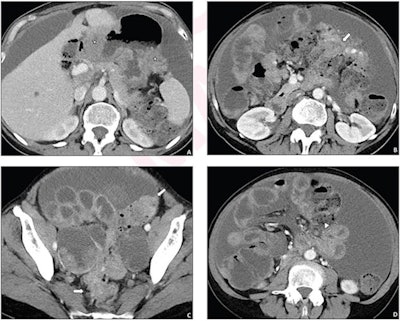

CT is the current gold standard for assessing tumor extent in ovarian cancer sufferers, and an accurate report is key for guiding surgeons' treatment planning, the team noted. Yet the traditional free-text radiology reports may not include findings that would best support this -- which is why a summary report that features a disease-specific checklist makes sense, the group explained.

Andrieu's team sought to compare the efficacy of simple versus synoptic reports via a study that included 205 patients who underwent contrast-enhanced abdominopelvic CT between June 2018 and January 2022 before being treated for advanced ovarian cancer. Before March 2020, CT exam readers generated 128 free text reports. After April 2020, they produced 77 synoptic reports that consisted of a list of 45 anatomic sites pertinent to the management of ovarian cancer.